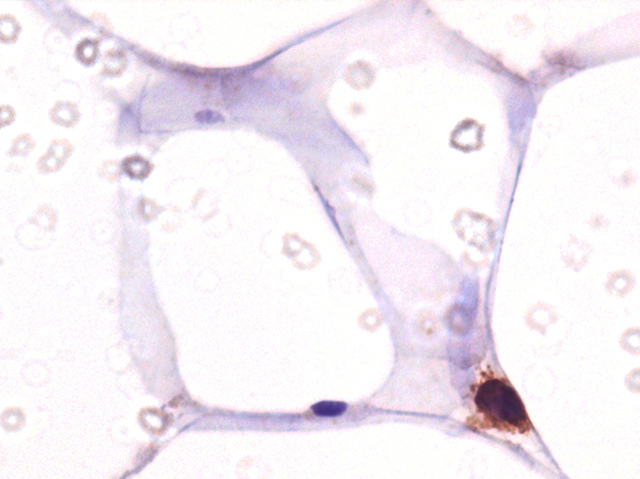

HIV Feels Fat

Anti-retroviral drugs have made a huge difference for people infected with HIV. Over recent decades they’ve turned HIV from a death sentence, when infection turns into full-blown AIDS, to a long-term chronic illness. And many people who are treated promptly will go on to live a normal lifespan. But although these drugs are good at keeping HIV under control, they don’t get rid of it completely so they’re not a true ‘cure’. Low levels of the virus hide in the body, causing chronic inflammation and related health problems. A new study shows that HIV-infected immune cells (the brown blob in this image) can lie low in a carrier’s body fat (the purple and white tissue), acting as a long-term viral reservoir. More fat probably means more viruses, so this raises an intriguing possibility to be researched: could helping infected people shed fat play a part in controlling their HIV levels?